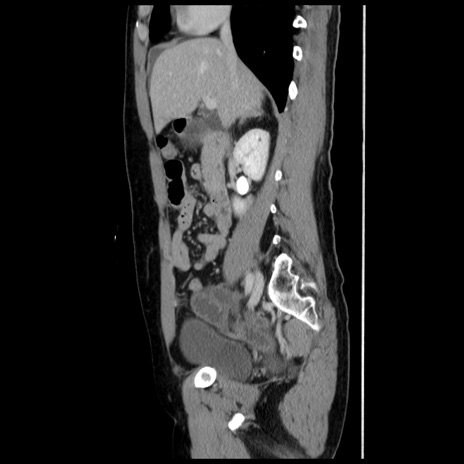

症例10(矢状断像)

【症例】 50歳代女性

【主訴】 腹痛

【現病歴】前日生レバーを食べた。今朝に排便あり。 昼前に突然発症の腹痛を生じ、当院救急外来を受診した。

【既往歴】 子宮筋腫にてで子宮全摘後

【身体所見】 意識清明、腹部:平坦、軟、下腹部やや左を中心に圧痛・反跳痛あり、筋性防御あり

【データ】WBC 7800、CRP 0.07